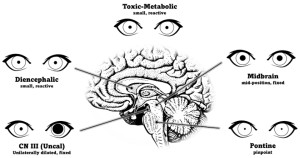

Pupillary response

The pupillary light reflex is easily tested and can help with localizing the cause of the coma. To perform this test, first, observe the pupil size in ambient and dim lighting for anisocoria. Shine a bright light into one eye and then alternate between each eye, observing both pupils for any reactivity. Note if the pupils react briskly, sluggishly, or have no response. Swinging the flash light from one eye to the other can detect a relative afferent pupillary defect.

A normal pupil examination includes equal sized (i.e., isocoric) pupils in light and dark illumination; normal direct and consensual pupillary constriction to light stimulus; round and regular pupils; an intact near stimulus (requires voluntary effort), and the absence of a RAPD.

- Unilateral dilated and unreactive pupil

- A unilateral dilated, fixed, and nonreactive pupil in a comatose patient can be an urgent finding (i.e., Hutchinson pupil) from compression of the third nerve at the Kernohan notch due to uncal herniation. Any compressive lesion along the third nerve (e.g., ruptured posterior communicating artery aneurysm) can cause coma. Inadvertent pharmacologic dilation (e.g., atropine drops, scopolamine patch, atropine based inhalers) can mimic the Hutchinson pupil. Administration of topical 1% pilocarpine will not constrict an atropinized, pharmacologically dilated pupil and can be used as a pharmacologic test to differentiate from third nerve palsy.[15]

- Bilateral pinpoint pupils

- Typically dorsal pontine injury

- Injuries such as pontine hemorrhage can disrupt the pupillodilator pathway causing near-maximal constriction[15]

- Bilateral, small, but reactive pupils

- a nonspecific finding

- a very resistant response in the absence of structural damage to the brain and can be suggestive of metabolic or systemic pharmacologic etiologies

- injury to the diencephalon and many toxins and drugs have a similar effect[15]

- Unilateral, small, but reactive pupil

- Horner syndrome can be localized to damage to the ipsilateral oculosympathic pathway (hypothalamus to posterolateral brainstem (first order neuron) descending caudally to ciliospinal center of Budge (cervical C8 to thoracic T2 level in spinal cord), ascending the sympathetic chain to the internal carotid artery then the cavernous sinus, cranial nerve VI then CN V1 to the eye. In addition to the miosis, anisocoria worse in the dark, the presence of ipsilateral ptosis, upside down ptosis, and anhidrosis supports the diagnosis of Horner syndrome. Topical confirmation with cocaine or apraclonidine drops might confirm the Horner syndrome.[15]

- Bilateral fixed and dilated pupils

- suggests CN III dysfunction as seen in bilateral infarction of the dorsal midbrain

- the size of the pupils can be either large or mid-position depending on the preservation of sympathetic tracts[15]